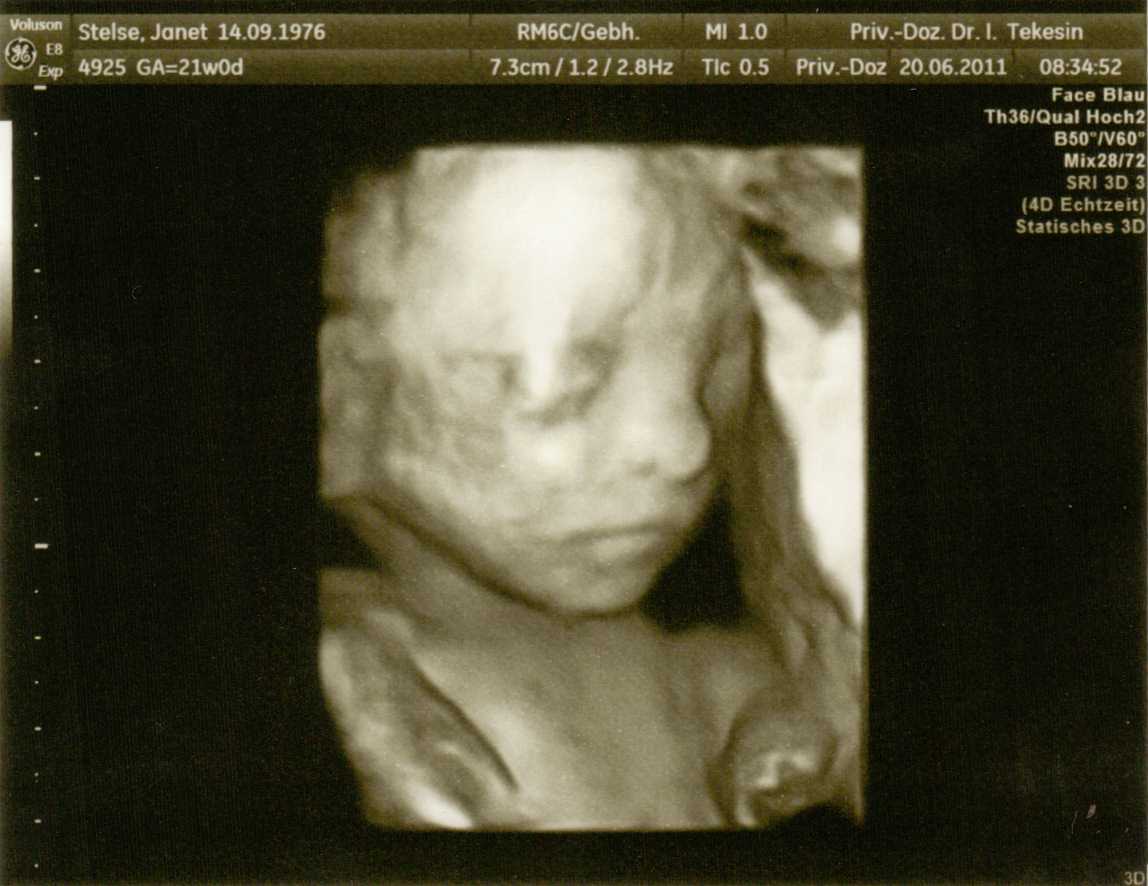

Teddylove09-wie weit bist Du denn? Und Du weißt also auch noch nicht was "es" wird? Also ich bin heute 20+6 und weiß es auch noch nicht! Bin doch sooooo neugierig und kann es kaum abwarten. Ich finde wir sind spät dran mit dem Outing und ich habe nicht gerade HIER geschrien, als Geduld verteilt wurde.

Hier ist außer unfassbarer Stress alles super. Baby wächst und gedeiht und ist seeehr aktiv! Tritt mich täglich mehrfach